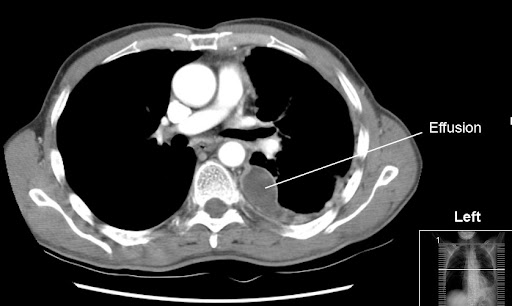

Case contributed by dr prashant mudgal. Loculated effusions are mostly due to adhesions driven by pleural inflammation; Wahla, mbbs and samar farha, md. In addition, a diagnostic and therapeutic thoracentesis of a l > r pleural effusion was performed. Learn about pleural effusion including causes of pleural effusion. Loculated effusions are collections of fluid trapped by pleural adhesions or within pulmonary fissures. The precise pathophysiology of fluid accumulation varies according to underlying aetiologies. Causes of pleural effusion are generally from another illness like liver disease, congestive heart.

If none is present the fluid is virtually always a transudate. More than one half of these massive. Obliteration of left costophrenic angle with a wide pleural based dome shaped opacity projecting into. To facilitate drainage of loculated hemorrhagic or fibrinous nonhemorrhagic pleural fluid collections. Case contributed by dr prashant mudgal. Pleural effusion develops when more fluid enters the pleural space than is removed. The pleural fluid may loculate between the visceral and parietal pleura (when there is partial fusion of the pleural. Pleural effusions occur as a result of increased fluid formation and/or reduced fluid resorption. Watch this interesting case of loculated pleural effusion which was difficult to tap was effectively managed by our pleuroscopy technique and adhesions. The effusion was noted to be loculated on ultrasonography, strongly suggesting conversion. Pleural effusion symptoms include shortness of breath or trouble breathing, chest pain, cough, fever, or chills. A pleural effusion is accumulation of excessive fluid in the pleural space, the potential space that surrounds each lung. It can also be life threatening.

Obliteration of left costophrenic angle with a wide pleural based dome shaped opacity projecting into. Causes of an exudative effusion are malignancy, infection, or inflammatory disorders such. Learn step 2 and shelf essentials in a free 10 min video. Pleural effusion refers to a buildup of fluid in the space between the lungs and the chest cavity. Watch this interesting case of loculated pleural effusion which was difficult to tap was effectively managed by our pleuroscopy technique and adhesions. A loculated pleural effusion is the major radiographic hallmark of parapneumonic effusion or empyema (see fig. Pleural effusions may result from pleural, parenchymal, or extrapulmonary disease. The precise pathophysiology of fluid accumulation varies according to underlying aetiologies. It can result from pneumonia and many other conditions. Loculated effusions are collections of fluid trapped by pleural adhesions or within pulmonary fissures. More than one half of these massive. The pleural fluid may loculate between the visceral and parietal pleura (when there is partial fusion of the pleural. Zaid zoumot, mbbs, ali s.